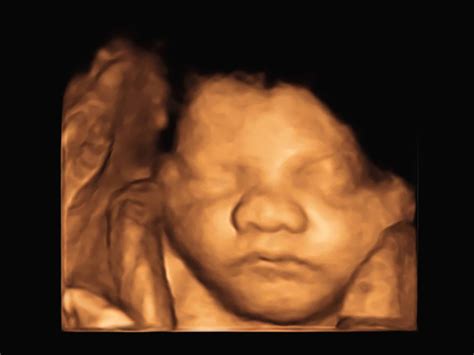

Learn what to look for regarding Down Syndrome on ultrasound. Discover how specialized screenings, including nuchal translucency scans and prenatal diagnostic markers, help detect potential chromosomal abnormalities. Our expert guide explains the soft markers, common ultrasound findings, and next steps for parents seeking clarity during pregnancy to ensure informed healthcare decisions for both mother and baby.

TitleDown Syndrome Baby Ultrasound 2D/3D/4D Ultrasound Of The Fetal Face In